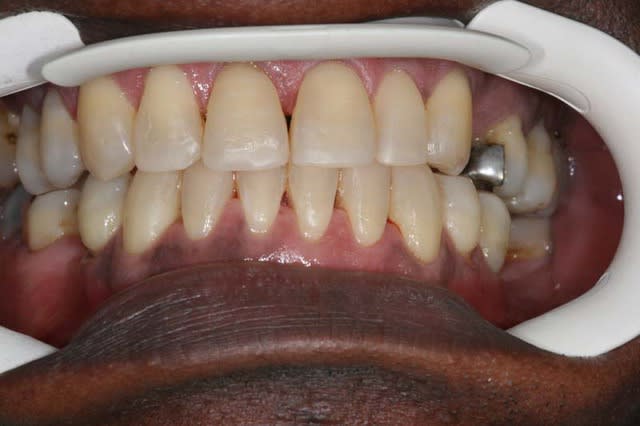

Cas terminé

@+ Bjc.

9 zusb4q - Eugenol

10 p0hjed - Eugenol

rectification: voici son profil fin de TTT.,